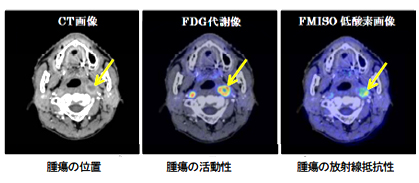

Ct検査よりがん組織と正常組織の区別が明確でct検査とは異なる情報からがんの深さや広がりリンパ節への転移の有無を調べます 7超音波エコー検査 首の表面から超音波をあ てそのはね返りをモニターで見ながら確認. 下咽頭癌の進展範囲を読影する際のチェックポイント 腫瘍の最大径 喉頭への進展の有無 軟骨浸潤の有無 上下方向への進展範囲の決定中咽頭頸部食道 軟部組織浸潤の有無特に梨状癌 梨状窩尖部への進展の有無.

頭頸部癌 最近の診断 治療の進歩 耳鼻咽喉 頭頸科 順天堂医院

放射線治療 頭頸部がん 九州大学病院のがん診療 九州大学病院 がん